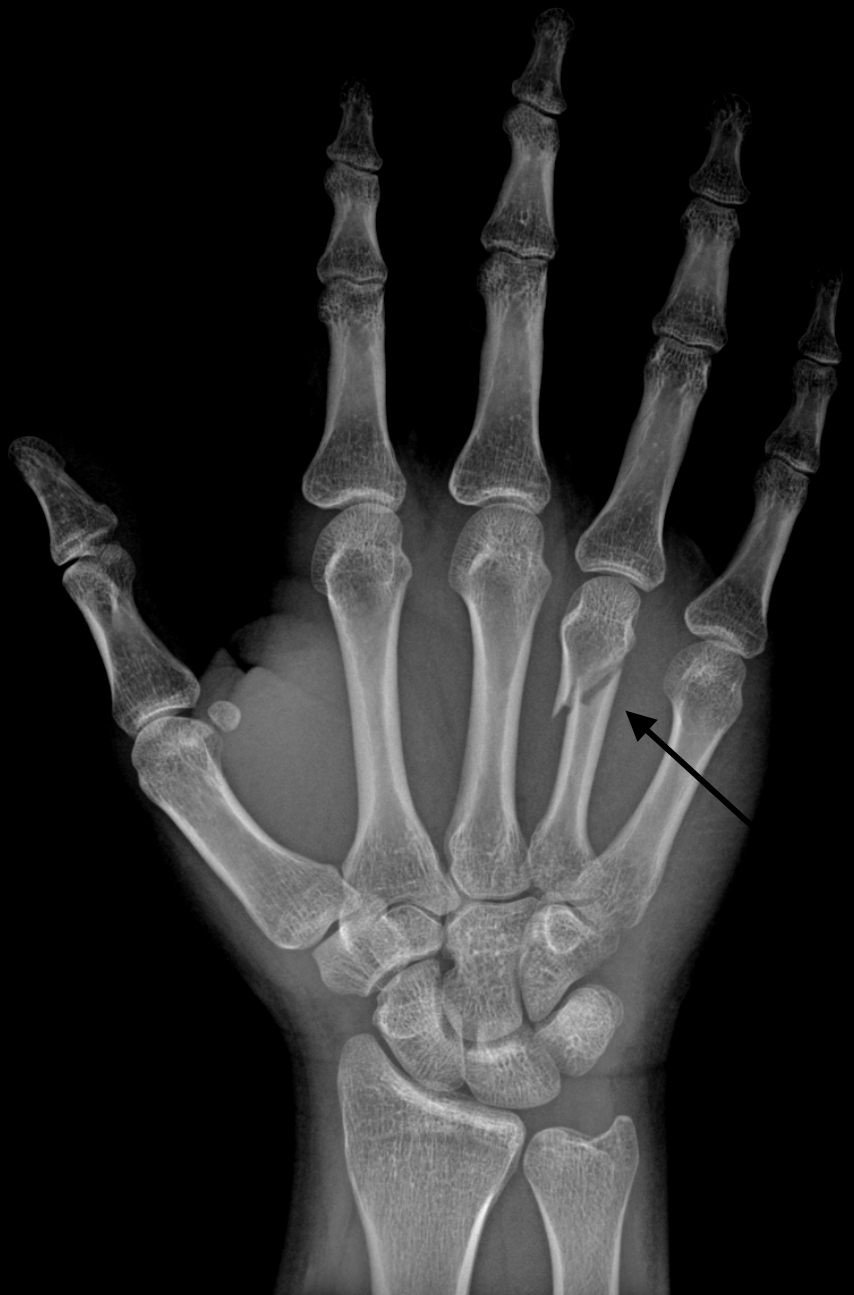

- Fracture of the fourth or fifth metacarpal bones caused by an axial load, typically from punching a person or object.

Imaging

- Typically seen on AP or lateral hand radiographs